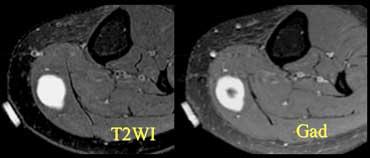

Bệnh nhân có khối sờ thấy được. Đã đặt marker. Tổn thương ngấm thuốc tương phản từ do u xơ thần kinh.

Cần lưu ý rằng không phải mọi tổn thương tăng tín hiệu trên chuỗi xung T2W đều là dịch.

Cần nghi ngờ khi có hình ảnh trông giống như ổ dịch nhưng không nằm ở vị trí thông thường của túi hoạt dịch, nang hoặc ngách khớp.

Nên tiêm Gadolinium để phân biệt tổn thương dạng nang với tổn thương đặc.